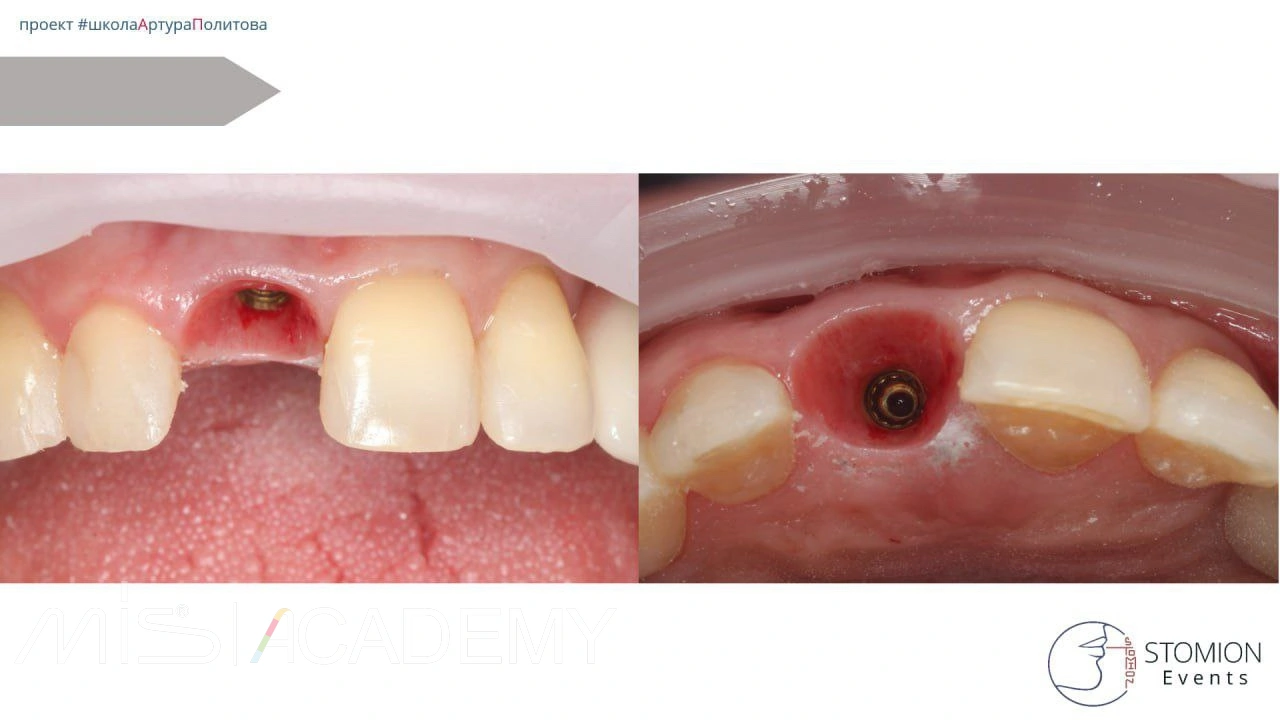

Атравматичное удаление зуба 1.1 с использованием системы Benex. Тип лунки — I (интактная).

— Выполнена одномоментная установка имплантата MIS C1 3,75 × 13 мм с коннектом 3 мм. Зазор более 2 мм.

— Выполнена немедленная нагрузка с использованием позиционера.

Снятие швов — через 9 суток.

Через 1 год — финишная ортопедическая реставрация на имплантате с уровня коннекта.